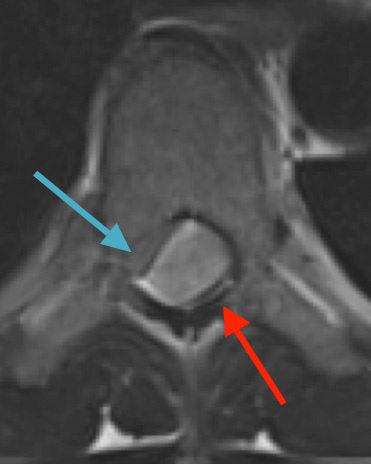

Preoperative MRI T1w demonstrating a large enhancing tumor (red arrow) causing severe cord compression and displacement (blue arrow)

Postoperative MRI T1w demonstrating interval resection with cord re-expansion (blue arrow)

Postoperative MRI T2 illustrating the restoration of CSF surrounding the cord (blue arrow)